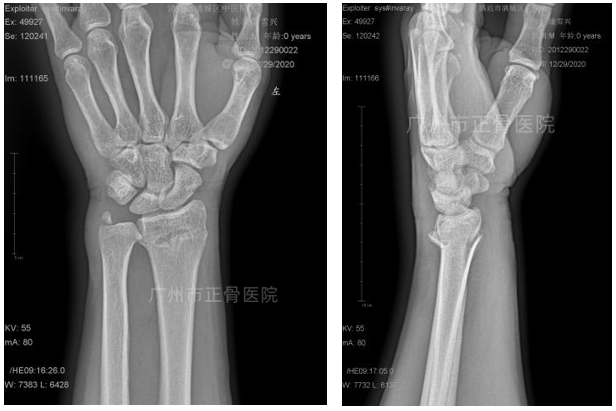

急诊拍摄X线片示:“左侧桡骨远端骨折,骨折断端嵌插短缩,向掌侧成角,合并尺骨茎突骨折。”

▲复位前,骨折移位